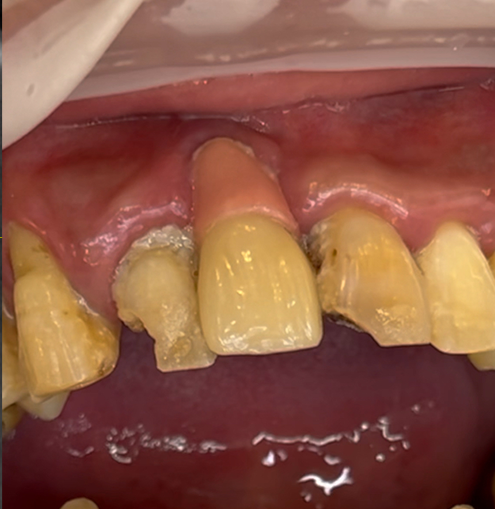

영상에서 보시는 것처럼 치료전 치아상태가 아주 좋지 않습니다. 치조골이 모두 녹아서 치아들이 많이 흔들릴뿐 아니라 치석과 프라그가 치아에 잔뜩 붙어있습니다. 이런 상태를 보았을 때 우리는 전체임플란트 치료후 위생관리를 더 신경쓰게 해야 한다는 것을 생각하게 됩니다.

이 환자분은 40대의 젊은 남성이었는데 아무래도 치아가 하나둘 망가지면서 관리를 포기한 상태였던 거 같습니다. 입 안에 임플란트가 앞니에 하나 있었는데 해당 임플란트는보기에 흉하게 만들어져 있을 뿐 아니라 이미 임플란트주위염이 생겨져 있어서 해당 임플란트도 다른 치아처럼 제거를 하기로 했습니다.